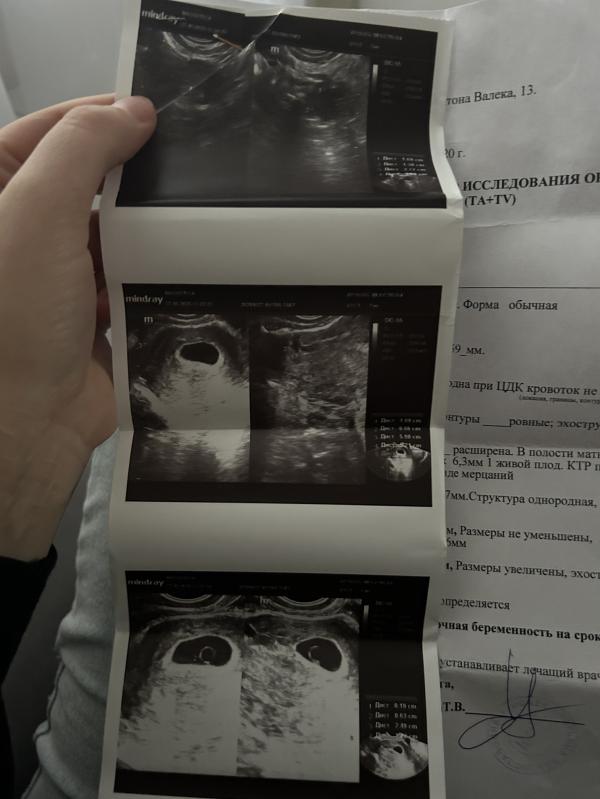

Девочки два узи, говорят что беременность анэмбриональная, срок 7-8 недель

Ходила сегодня платно на повторное узи сказали что видят два желтых мешка( большие) но эмбрионы не визуализируются, говорят шансов нет идти на чистку, что делать не знаю. Может у кого-то было такое.

(Изначально на первом узи не сказали что два мешочка)